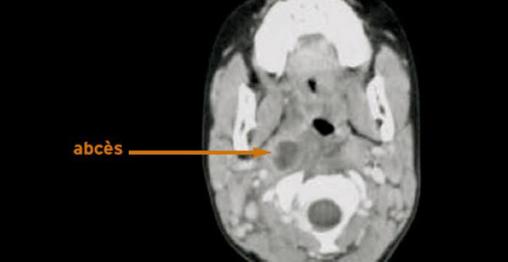

Abcès parapharyngé droit

Scanner cervical avec injection de produit de contraste.